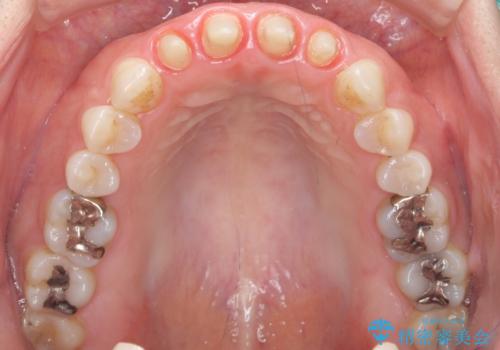

- 10年前に美容外科クリニックで前歯を治療したところ、あまりに不自然で逆にコンプレックスになってしまったことを主訴に来院された患者様です。

前歯4本の被せものは連結されており、不自然なだけではなく清掃性も悪く歯茎が著しく腫脹していました。

レントゲンを撮影したところ土台の植立も不十分であったため、土台からやりかえることにしました。